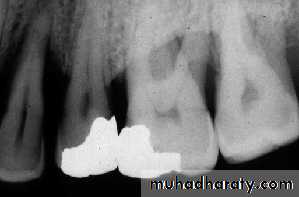

A-Calculus:

It is a stone-like concretion that forms on the crown & roots of the teeth due to the calcification of bacterial plaque.

Its appear as radiopaque on the dental radiograph.

its either pointed or irregular radiopaque projection extending from the proximal root surface.

Calculus may be seen as a ring-like radiopacity encircling the cervical portion of the tooth.